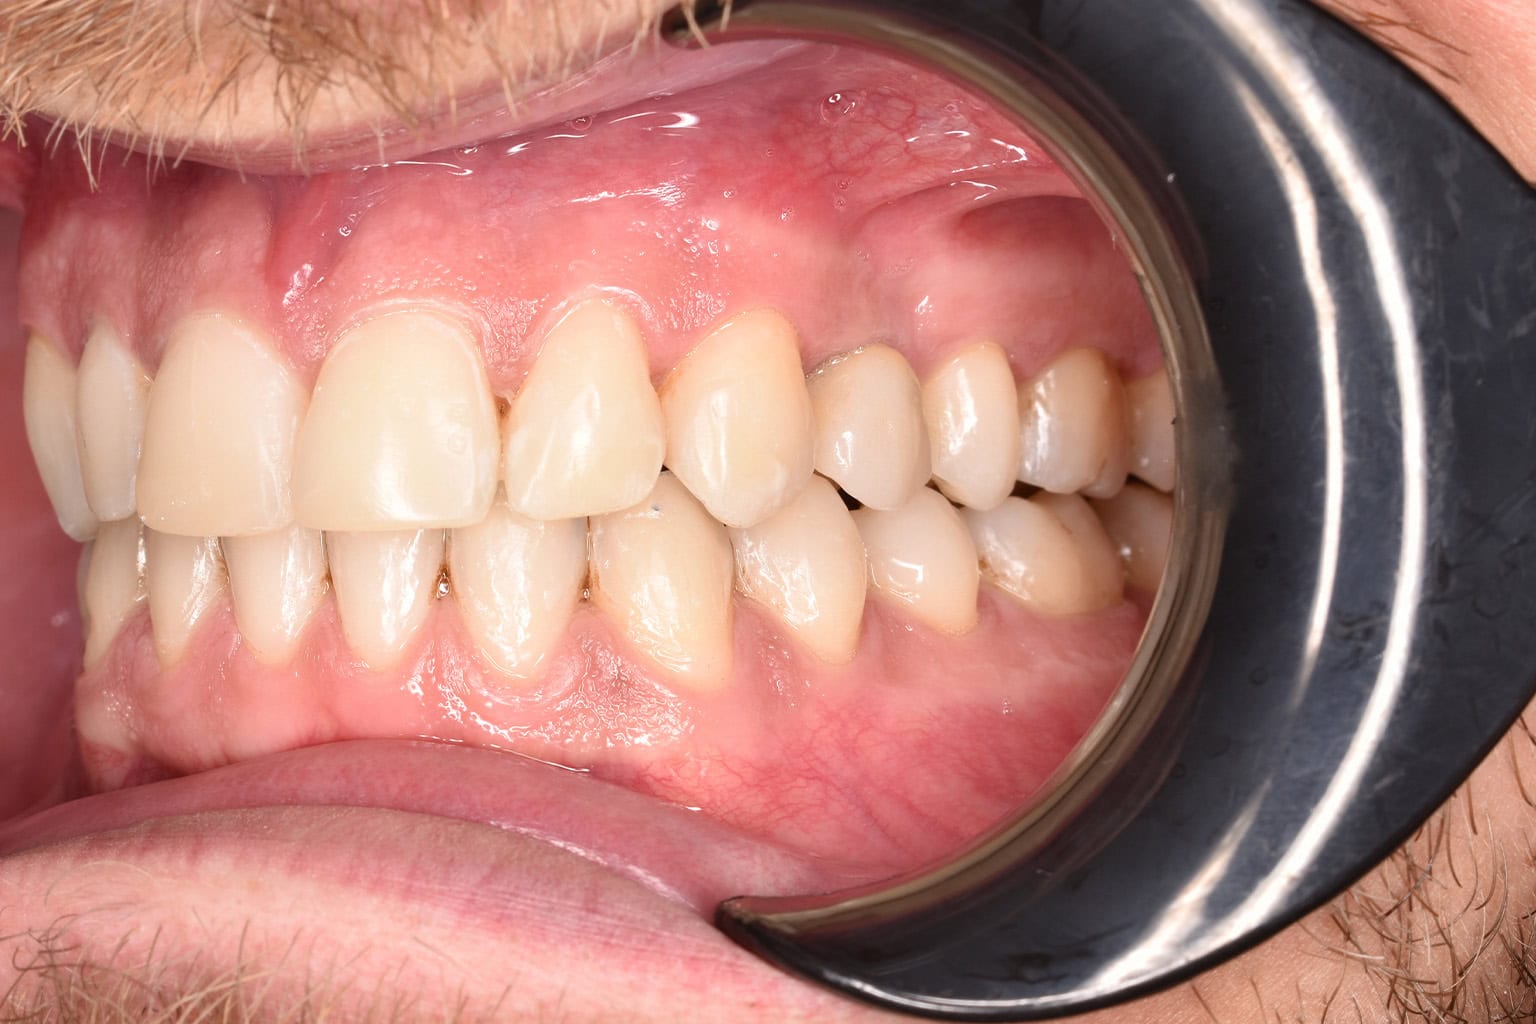

Vorher-Nachher-Ergebnisse

Echte Ergebnisse. Echte Menschen.

Jede Behandlung bei TIEFBLAU Kieferorthopädie ist so individuell wie der Mensch dahinter. In unserer Vorher-Nachher-Galerie zeigen wir Ihnen echte Behandlungsergebnisse aus unserer Praxis in der Kölner Südstadt: Schonend erzielt, präzise geplant und mit dem Anspruch, den wir seit über 40 Jahren an jede Behandlung stellen.

Die Bilder geben Ihnen einen Eindruck davon, was moderne Kieferorthopädie leisten kann, ob bei Kindern, Jugendlichen oder Erwachsenen.

Der sichtbare Unterschied

Dokumentiert. Überzeugend. Nachhaltig.